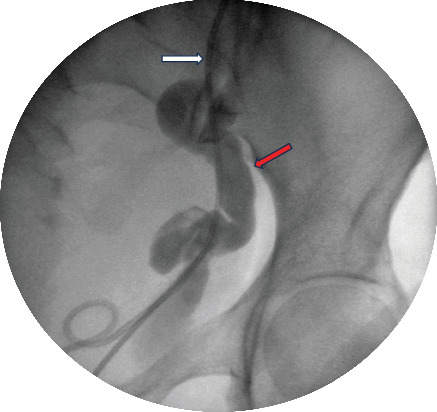

Duplex renal collecting system is a relatively common congenital abnormality affecting equally both pelvicalyceal systems. Although usually it is an incidental finding, it can cause significant problems to the patients such as recurrent urinary tract infections, hydronephrosis, and lithiasis. In this study, we describe an interesting surgical management option for a patient with upper moiety hydronephrosis and lithiasis of the aberrant ureter, achieving resolution of the hydronephrosis and complete removal of the calculus. A 49-year-old female patient presented with symptoms of left colicky pain. During the initial investigation, a left-sided duplex renal collecting system with severely hydronephrotic upper pole moiety and grossly dilated tortuous ureter with distal calculus and ectopic insertion to urinary bladder was identified. On cystoscopy, the upper moiety ureteric opening was identified distally to the urethral sphincter. Under ultrasound guidance, endoscopic transvesical resection was performed distal to the stented lower moiety ureteric orifice, resulting in the identification of the stone and extraction. Short- and long-term follow-up demonstrated no recurrence of the stone and significant resolution of the hydronephrosis. In conclusion, in this case report, we describe an unusual anatomical variation of the upper moiety outflow, and we introduce a new technique of intravesical ultrasound-guided removal of an obstructive calculus.